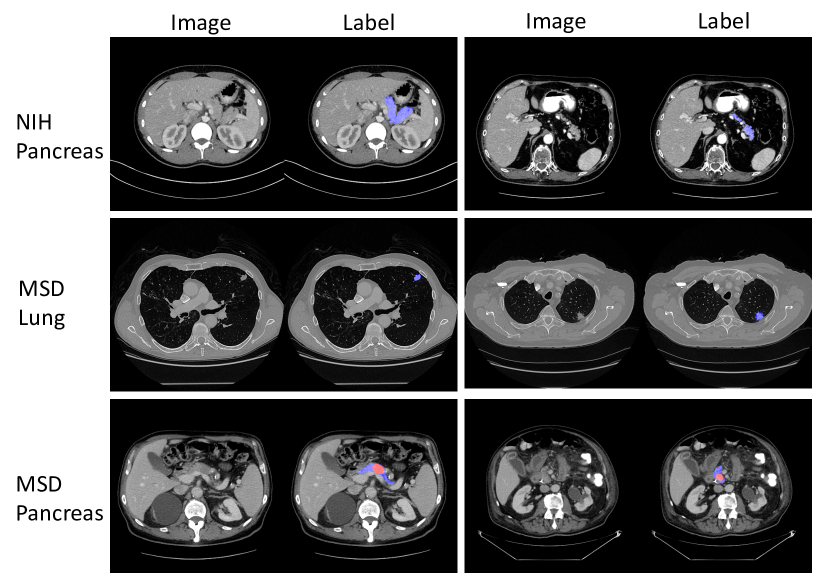

In this work, we focus on the volumetric medical image segmentation. Taking the pancreas and lung tumors segmentation from CT scans as an example as shown in Fig. 1, the main challenges lie in several aspects: 111) the small size of organs with respect to the whole volume; 222) the large variations in location, shape and appearance across different cases; 333) the abnormalities, i.e., the pancreas and lung tumors, can change the texture of surrounding tissues a lot; 444) the anisotropic property along z𝑧z-axis, which make the automatic segmentation even harder.

Refer to caption

Figure 1: Typical examples from NIH Pancreas [21] in the 111st row, MSD Lung Tumors [24] in the 222nd row and MSD Pancreas Tumors [24] in the 333rd row. Two slices of different cases are randomly chosen from each dataset. Normal Pancreas regions are masked as blue and abnormal pancreas regions are masked as red. The lung cancers are masked as blue. Best viewed in color.